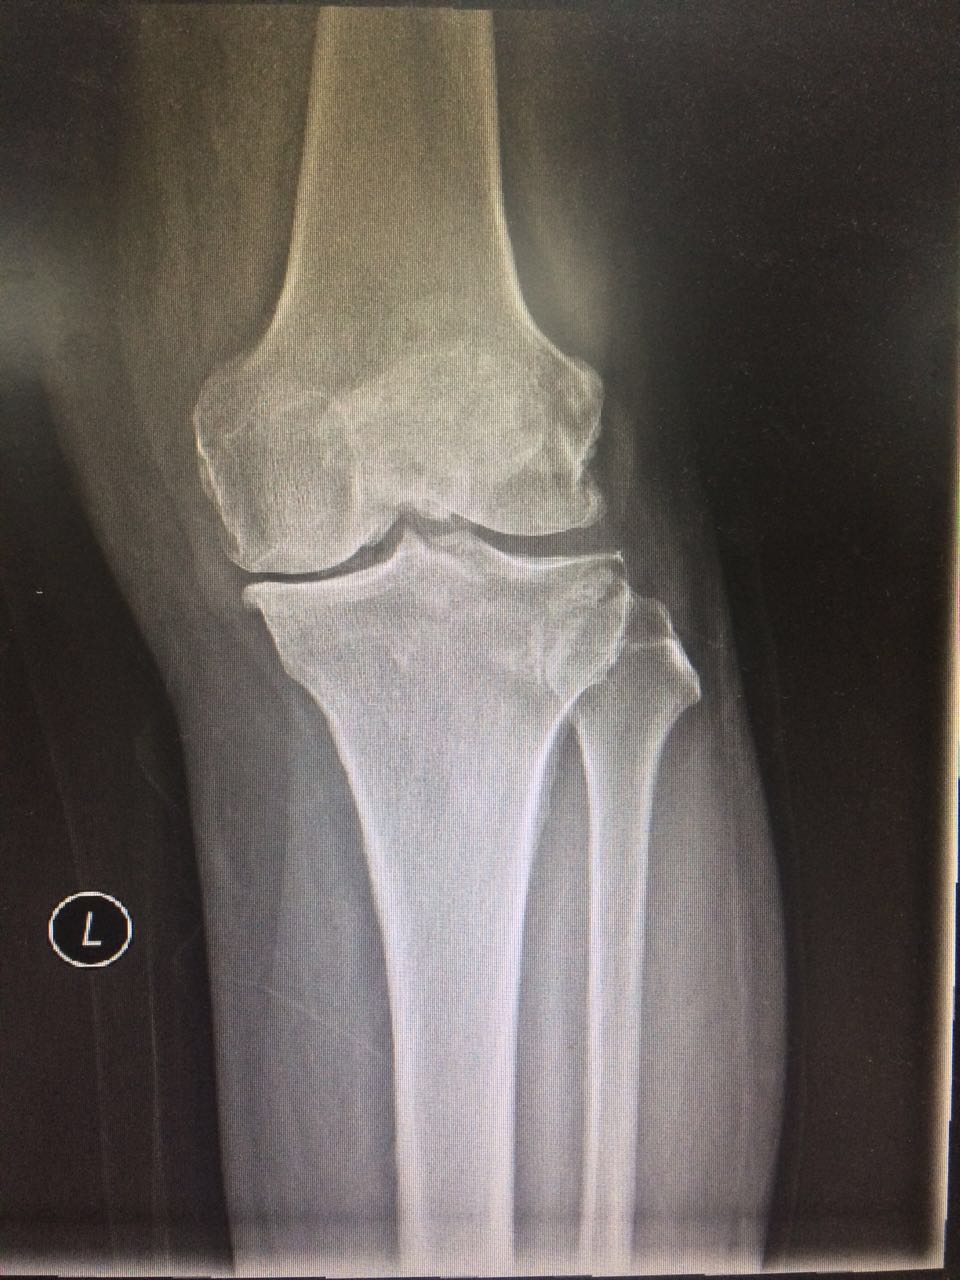

双膝 DR:关节面硬化,关节间隙变窄,游离体。

MRI:膝关节少量积液、半月板损伤,软骨下缺血坏死。

诊断:双膝关节骨性关节炎

附:患者影像学资料: